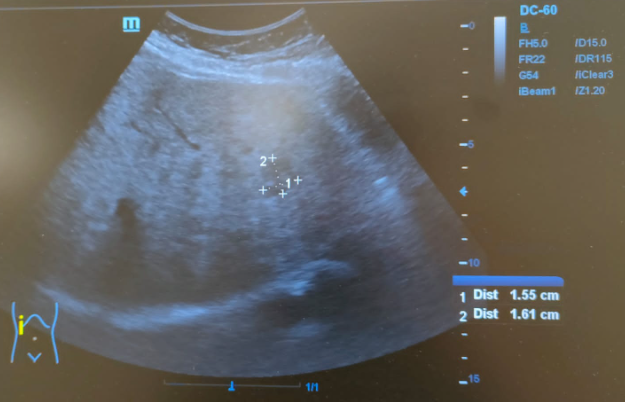

Hallazgos ecográficos

Hígado de tamaño normal, contornos ligeramente nodulares, alteración de la ecoestructura compatible con hepatopatía crónica. Nódulo hipoecoico de contornos irregulares en lóbulo hepático izquierdo de 16x24mm sin captación Doppler.